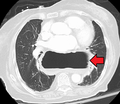

A hiatus hernia as seen on CT